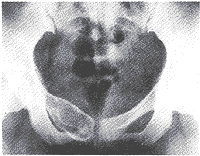

動脈瘤樣骨囊腫--X片平片示:①偏心型:發生於長骨的多為此型,病灶偏於骨幹的一側,呈吹氣臌樣膨出至骨外,內有骨性間隔,似蜂窩狀。②中心型:呈溶骨性囊狀透明影,最大直徑可達10cm。囊內含有粗細不均的骨性間隔,呈多房狀,向橫的方向擴張。③位於扁骨時,病灶呈囊狀膨脹。位於脊柱者除呈囊狀膨脹外還可跨越椎間盤,侵入鄰近椎體。動脈瘤樣骨囊腫如發生於椎體等少見的短管骨,X線檢查應注意與骨囊腫、巨細胞瘤、血管瘤、孤立性內生軟骨瘤和囊狀骨纖維結構不良等鑑別。上述各病均可引起短骨囊狀骨質破壞,骨皮質膨脹變薄,其內呈蜂房狀,但骨囊腫、孤立性內生軟骨瘤和囊狀骨纖維結構不良病變的膨脹程度多不如動脈瘤樣骨囊腫,也多無本病所見的典型的皂泡樣改變。血管瘤具有典型的柵欄狀骨質改變,病灶內鈣化,以及MRI信號,血管瘤燈泡征特性和慢進慢出的強化表現。孤立性內生軟骨瘤雖好發於手足短管骨,但以手部發病率為高,多位於乾骺或骨幹內,呈輕度膨脹,易骨折,特徵性表現為囊內有瘤軟骨的鈣化,骨囊腫病灶內部多無骨嵴分隔及鈣化;單囊型骨纖維結構不良X線多呈較特徵性的毛玻璃樣改變,纖維組織易鈣化及骨化,多有硬化邊。對於少數影像學近似病例,傳統X線診斷難以定性,多需要CT或MRI進一步檢查。

動脈瘤樣骨囊腫都有典型的X線表現,位於四肢長骨的表現為病變在骨幹與乾骺端處,但不侵犯骨骺。其偏心性者向骨外突出如“氣球狀”膨脹囊腫表面為一薄層骨殼病變呈局限性透亮區,境界清晰邊緣有狹窄的硬化帶,其中有粗或細的不規則小粱分隔成蜂窩狀位,於骨中心者,向周圍擴張膨脹呈卵圓形,與骨的縱軸一致。位於脊椎的病變多在棘突椎板、橫突上亦膨出骨外。病變也可累及椎體,可導致病理性骨折少數病例病變可侵及鄰近椎體骶骨的病變也顯示膨脹改變有透亮區。CT掃描對確定病變是有幫助的,有時可顯示出病變內的液體平面有時可以顯示出動脈瘤樣骨囊腫特有的海綿樣外觀也可對其中的液體提供進一步信息可反映其富於血管的特性,更清楚顯示病變情況。